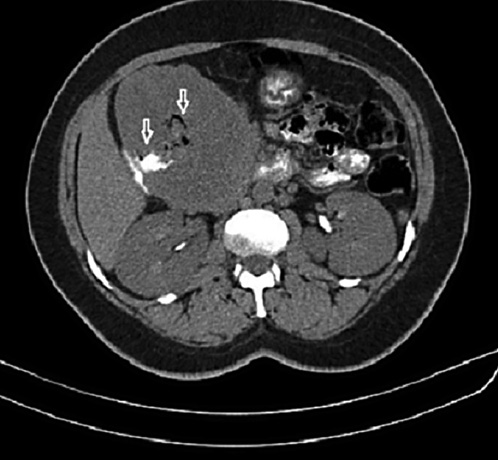

An abdominal computed tomography scan and magnetic resonance imaging showed a mixed solid and cystic lesion in the head of the pancreas approximately 12 × 10 cm in diameter. This mass was well delimited by a capsule that presented enhancement on the arterial phase. The tumor was in direct proximity to the duodenum and contained an air cavity within it that was filled by oral contrast, which was compatible with a fistulous tract (Fig. 2, 3). There was no dilation of the bile or pancreatic ducts on the magnetic resonance cholangiopancreatography.

Fig. 2 Computed tomography scan displaying a mixed solid and cystic lesion in the head of the pancreas approximately 12 × 10 cm in diameter. The tumor was in direct proximity to the duodenum and contained an air cavity within it that was filled by oral contrast, which was compatible with a fistulous tract (arrows).